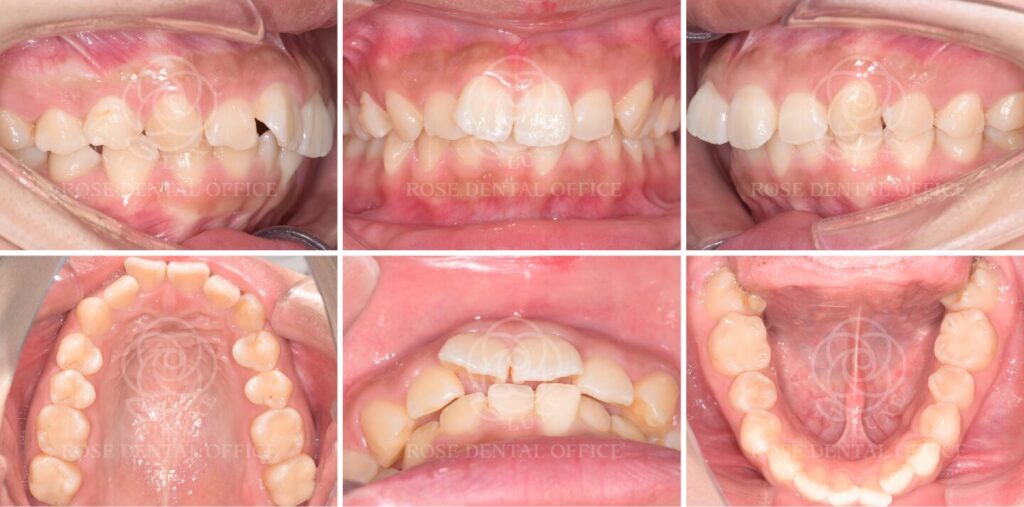

【前歯矯正】前歯のでこぼこを改善したインビザラインGO矯正治療 20代女性

Before

After

臼歯関係は良好で、目立たない矯正治療を希望されていました。大きな咬合異常は認められなかったため、前歯部を対象としたインビザラインGOによる矯正治療を行いました。